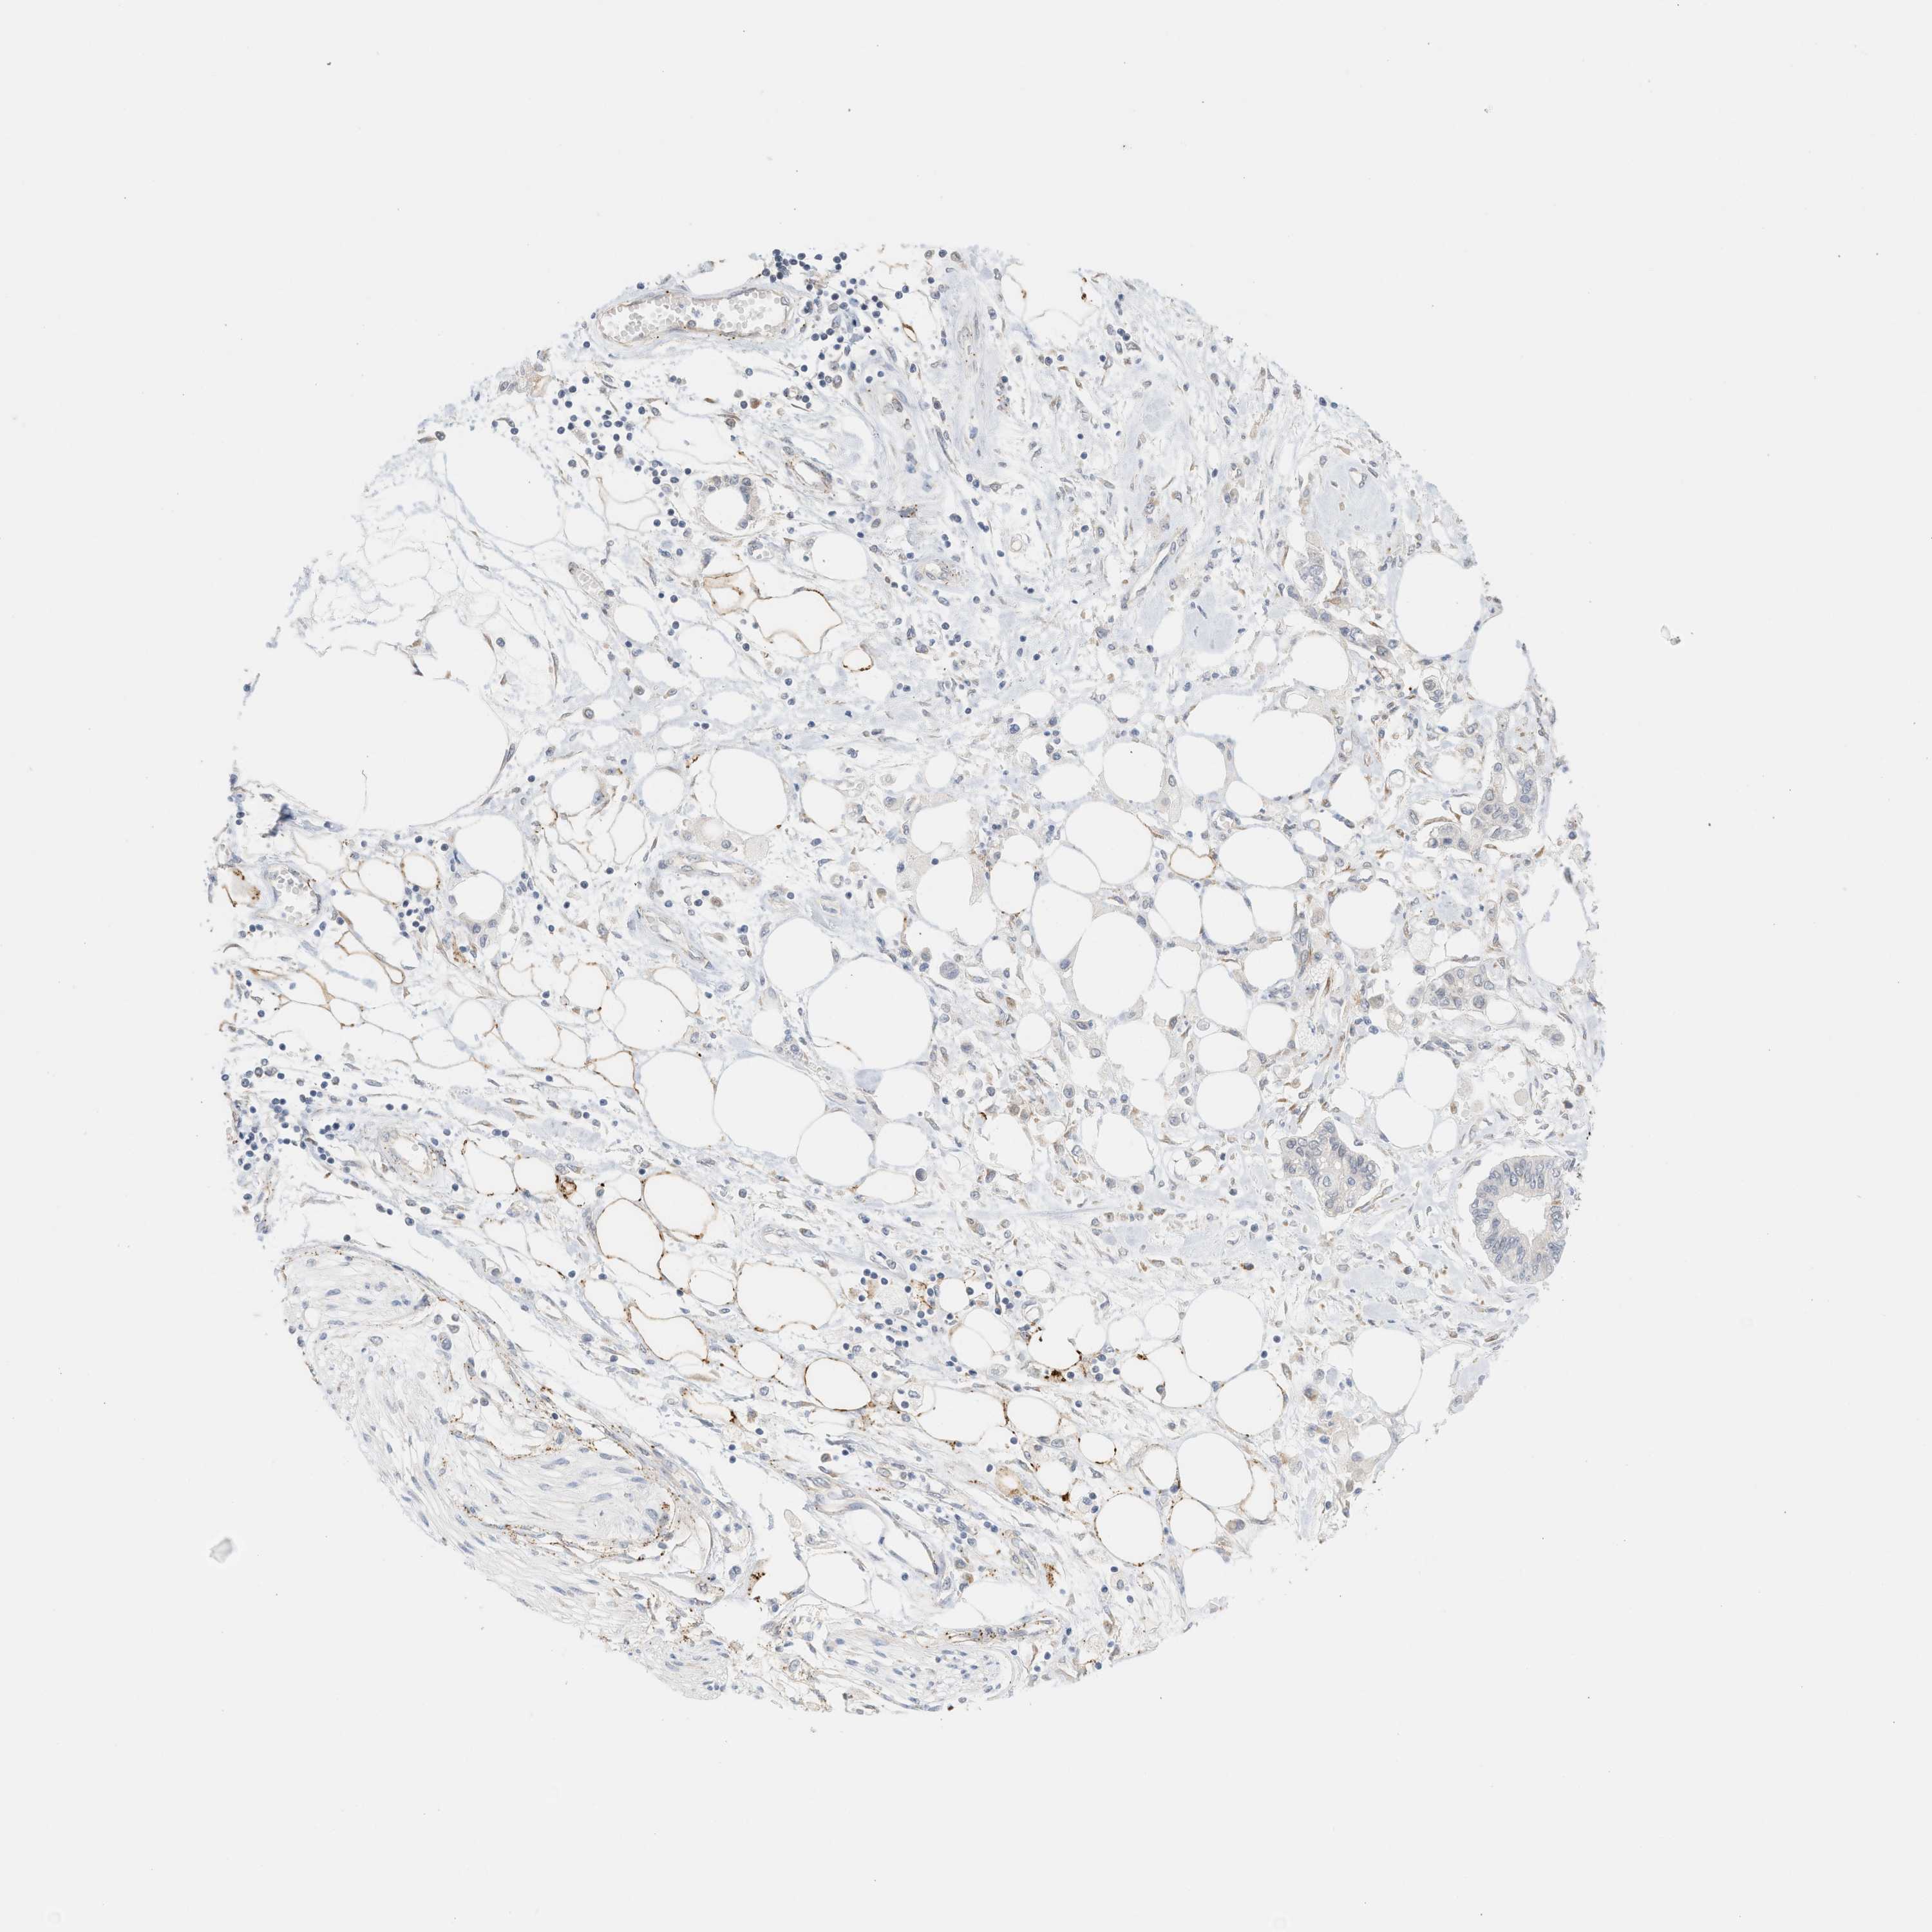

PANCREATIC CANCER - Protein expressioni

A mouse-over function shows sample information and annotation data. Click on an image to view it in a full screen mode. Samples can be filtered based on level of antibody staining by selecting one or several of the following categories: high, medium, low and not detected. The assay and annotation is described here.

Note that samples used for immunohistochemistry by the Human Protein Atlas do not correspond to samples in the TCGA dataset.

Antibody stainingi

Antibody staining in the annotated cell types in the current human tissue is reported as not detected, low, medium, or high, based on conventional immunohistochemistry profiling in selected tissues. This score is based on the combination of the staining intensity and fraction of stained cells.

Each image is clickable and will lead to virtual microscopy that enables deeper exploration of all samples and also displays staining intensity scores, fraction scores and subcellular localization as well as patient and tissue information for each sample.

Antibody HPA016573

Staining

High

Medium

Low

Not detected

Intensity

Strong

Moderate

Weak

Negative

Quantity

>75%

75%-25%

<25%

None

Location

Nuclear

Cytoplasmic/membranous

Cytoplasmic/membranous,nuclear

Adenocarcinoma, NOS